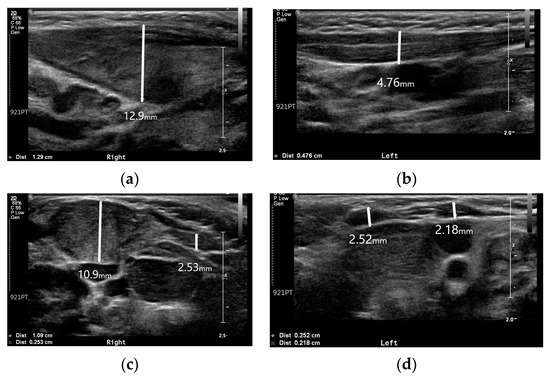

Ultrasound is the imaging modality of choice for radiographic evaluation of congenital muscular torticollis [8]. On ultrasound images, the SCM muscle appears as a relatively hypoechoic mass with echogenic lines; however, in cases of congenital muscular torticollis, the thickened SCM muscle mass can affect the size and signal intensity of the muscle. In conditions of congenital muscular torticollis, the affected SCM muscle looks thicker than the normal contralateral side, and the signal intensity of the muscle tends to be more hyperechogenic [8]. Neck ultrasonography exhibited asymmetric thickening of the right SCM muscle with hyperechogenicity (Figure 2). The thickness values of the SCM muscle at the right and left mid-levels were 12.9 and 4.7 mm, respectively, while the thickness values at the clavicular insertion point on the right and left sides were 10.9 and 2.1 mm. At the sternal insertion point, the right- and left-side thickness values were both 2.5 mm, and the baby exhibited prominent right-side muscular torticollis with fibromatosis coli.

Although idiopathic muscular torticollis was prominent, it can be viewed as a secondary change due to ipsilateral hemihypertrophy. According to a previous study by Hwang et al. [11], the average thickest part of the unaffected SCM muscle was 5.9 ± 1.1 mm, no more than 20% greater than that of the unaffected side. In this patient, the thickness values of the unaffected and affected sides were 4.7 and 12.9 mm, respectively. This discrepancy suggests that the SCM muscle was affected by ipsilateral hemihypertrophy.

There were no other underlying causes identified in this case that could affect the SCM muscle; however, the thickness of the affected SCM muscle was significantly thicker than the average reported by Hwang et al. As hemihypertrophy is defined as regional body growth asymmetry caused by differences in the growth of bone, soft tissue, or both, considering the definition of ipsilateral hemihypertrophy, hemihypertrophy could be the cause of muscular torticollis in this patient. After a few months of physical therapy, the remaining torticollis exhibited improvement, as did the hemihypertrophy. Without any other treatment, we presume that the treatment of torticollis had a beneficial effect on hemihypertrophy. The improvement of both conditions may suggest a relationship between muscular torticollis and hemihypertrophy in this patient. Moreover, radiologic and ultrasonographic evaluations did not reveal any sign of tumors or other conditions.

Figure 2. Neck ultrasonography of the SCM muscle: (a) Thickness of the right SCM muscle at mid-level; (b) Thickness of the left SCM muscle at mid-level; (c) Thickness of both SCM muscles at the clavicular insertion site; (d) Thickness of both SCM muscles at the sternal insertion site.